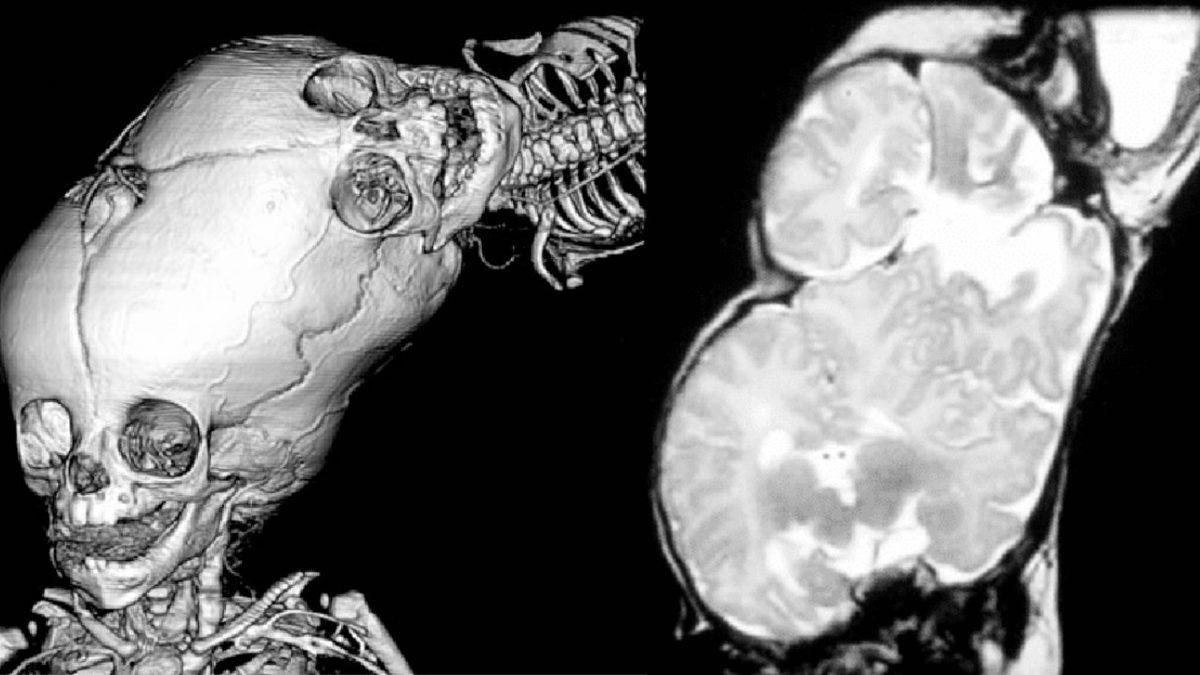

Bir vücutta iki kafanın gelişimi, tıpta Craniopagus paraziti olarak adlandırılır.

Bu durum yaklaşık 5 milyon doğumda 2-3 kez görülen, oldukça nadir rastlanılan parazitik bir ikiz türüdür ve bir embriyo olarak gelişmeye başlayan parazitik ikizlerden birinin kusursuz gelişimi, diğerinin ise son derece yetersiz büyümesi olarak ifade edilebilir.

“İki başlı bebek” ifadesiyle, bazı insanlar tek bir boyundan yan yana çıkan iki kafa hayal eder ancak bu vakada bebeğin ikinci kafası, diğerinin üzerinde büyür.

Bu yapıda vücuda bağlı kafanın üzerinde, ters bir biçimde bir kafa daha gelişir ve ikinci kafa, diğerinin üzerinde büyür. Elbette böyle bir durum, birtakım anormallikler de doğurur. İkinci kafanın kulakları duymuyor, dil ve alt çenesi de bir hayli küçük kalmıştır. Ancak her iki baş aynı boyuttadır ve birleşim bölgesi siyah kıllarla kaplıdır.

Ayrıca ikinci kafa, ana kafadan büyük oranda bağımsız çalışır. Örneğin çocuk ağladığında veya gülümsediğinde, başının üst kısmı her zaman etkilenmez ve duygu farklılıkları gözlemlenir. Çocuk uyurken ikinci baş kimi zaman uyanıktır ve gözleri, çevreyi izlercesine hareket eder.

Tüm bunların yanında ikinci kafanın, dış uyaranlara çeşitli tepkiler verdiği de tespit edilir.

İkinci baş bazı zamanlarda yüzünü buruşturur, memeye verildiğinde de dudakları emme hareketini gerçekleştirmeye çalışır. Ayrıca bol miktarda tükürük salgılar ve gözyaşı döker. Ancak kornea refleksleri zayıftır ve gözleri, ışığa zayıf tepkiler verir. Bu inanması güç gelişime rağmen bebek, daha farklı herhangi bir sağlık problemi yaşamamıştır.

Bu ajan, çürümüş bedeni parçalara ayırır ve beyinlerin birbirinden ayrı ve farklı olduğunu keşfeder.

Her beyin, beyin dokusunu ve omuriliği çevreleyen beyin zarlarının en kalın ve en dıştaki katmanı olarak adlandırılan dura materiyle sıkı bir biçimde kaplanmıştır ve beslenmeyi, başın üst kısmını ileten büyük damarlar sağlar.